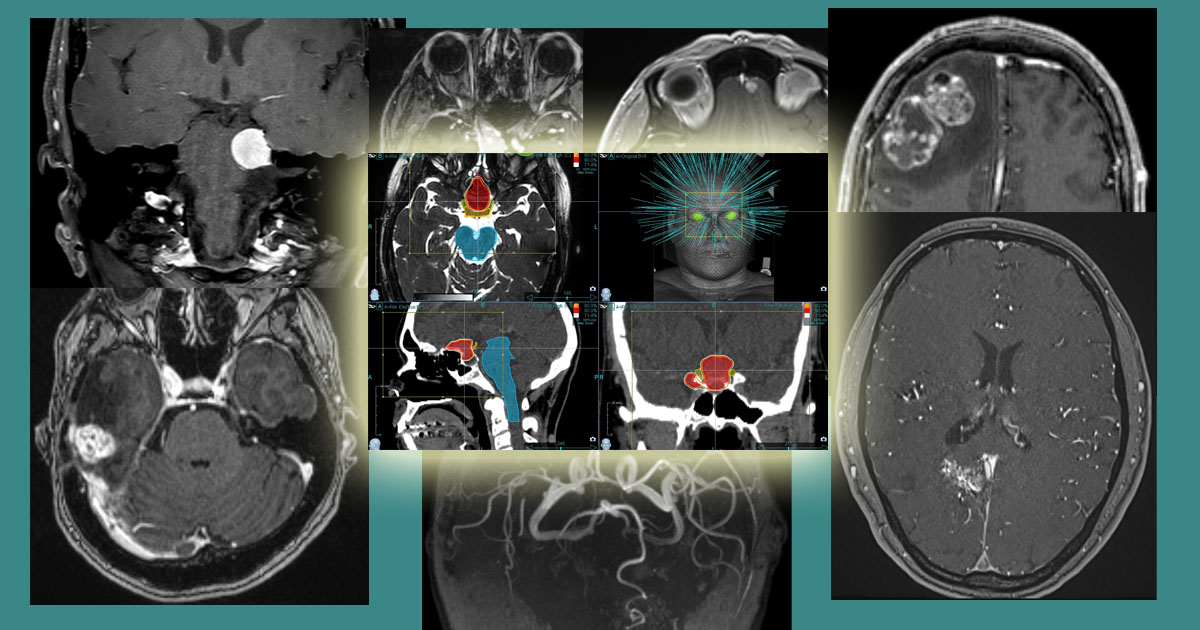

Πραγματικά Περιστατικά Θεραπείας με CyberKnife

Η καλύτερη απόδειξη για την αποτελεσματικότητα του CyberKnife είναι τα πραγματικά περιστατικά θεραπείας

Παραθέτουμε χαρακτηριστικά περιστατικά, όπου η εξαφάνιση ή συρρίκνωση των καρκινικών όγκων, των καλοήθων νεοπλασμάτων και των αρτηριοφλεβωδών δυσπλασιών είναι εντυπωσιακή μετά την ακτινοχειρουργική θεραπεία με CyberKnife.

Θα θέλαμε όμως να τονίσουμε ότι κάθε περίπτωση είναι μοναδική και κάθε πλάνο θεραπείας εξατομικευμένο.